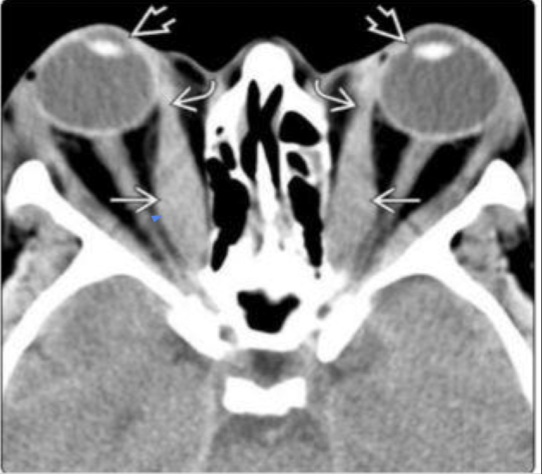

Hallazgos que podemos encontrar en una TC de orbitopatía tiroidea

• Agrandamiento de los músculos extraoculares

• Áreas de baja densidad debido a depósitos de glucosaminoglicano

• Exoftalmos

• Nervio óptico estirado

Q

¿qué enfermedad sospechas?

A

orbitopatía tiroidea